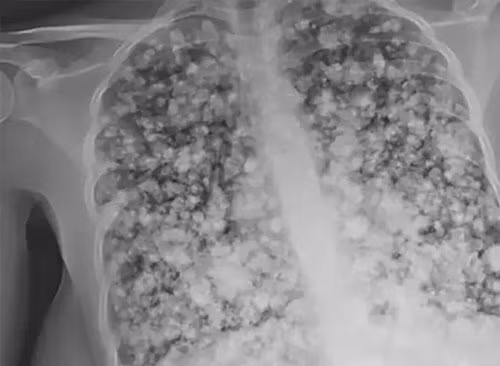

Phương pháp này giúp ổn định tình trạng của thiếu niên nhưng không hề giúp sức khỏe của cậu hồi phục. Phim chụp X-quang cho thấy, phổi của cậu thiếu niên đã trở thành phổi bỏng ngô, một dạng tổn thương phổi cực kỳ nghiêm trọng.

Điều đáng sợ hơn nữa là bác sĩ chẩn đoán phổi của cậu thiếu niên không thể chữa khỏi, chỉ khi được tiến hành ghép hai lá phổi mới có cơ hội phục hồi. Thậm chí nếu ca mổ thành công thì rất có thể, cậu thiếu niên cũng bị rút ngắn tuổi thọ hơn nhiều.